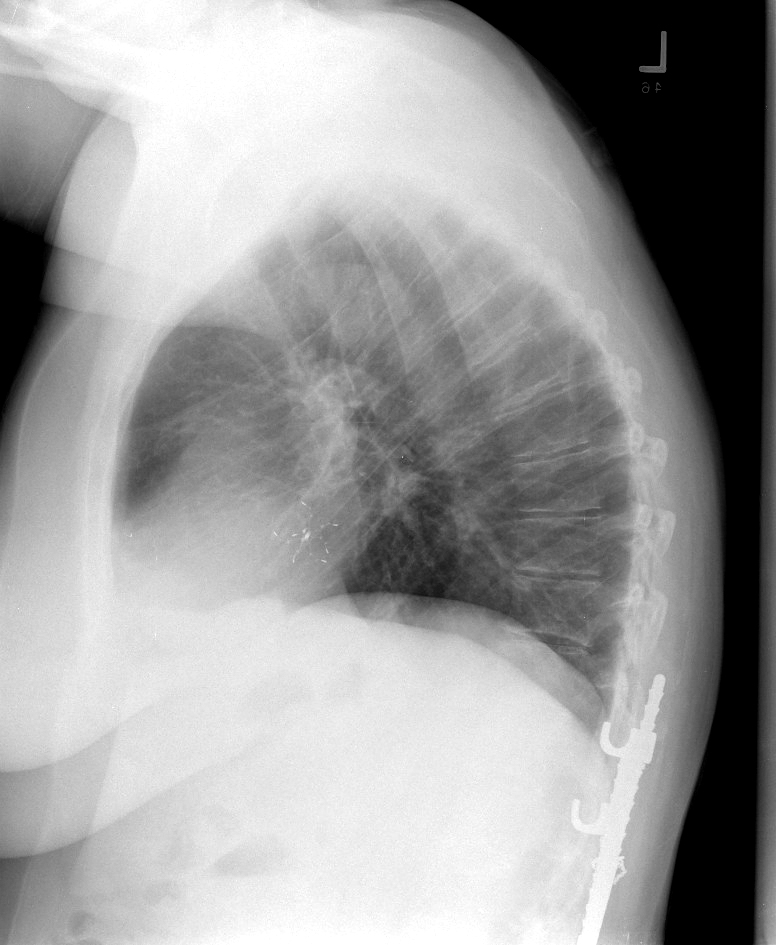

clamshell 1